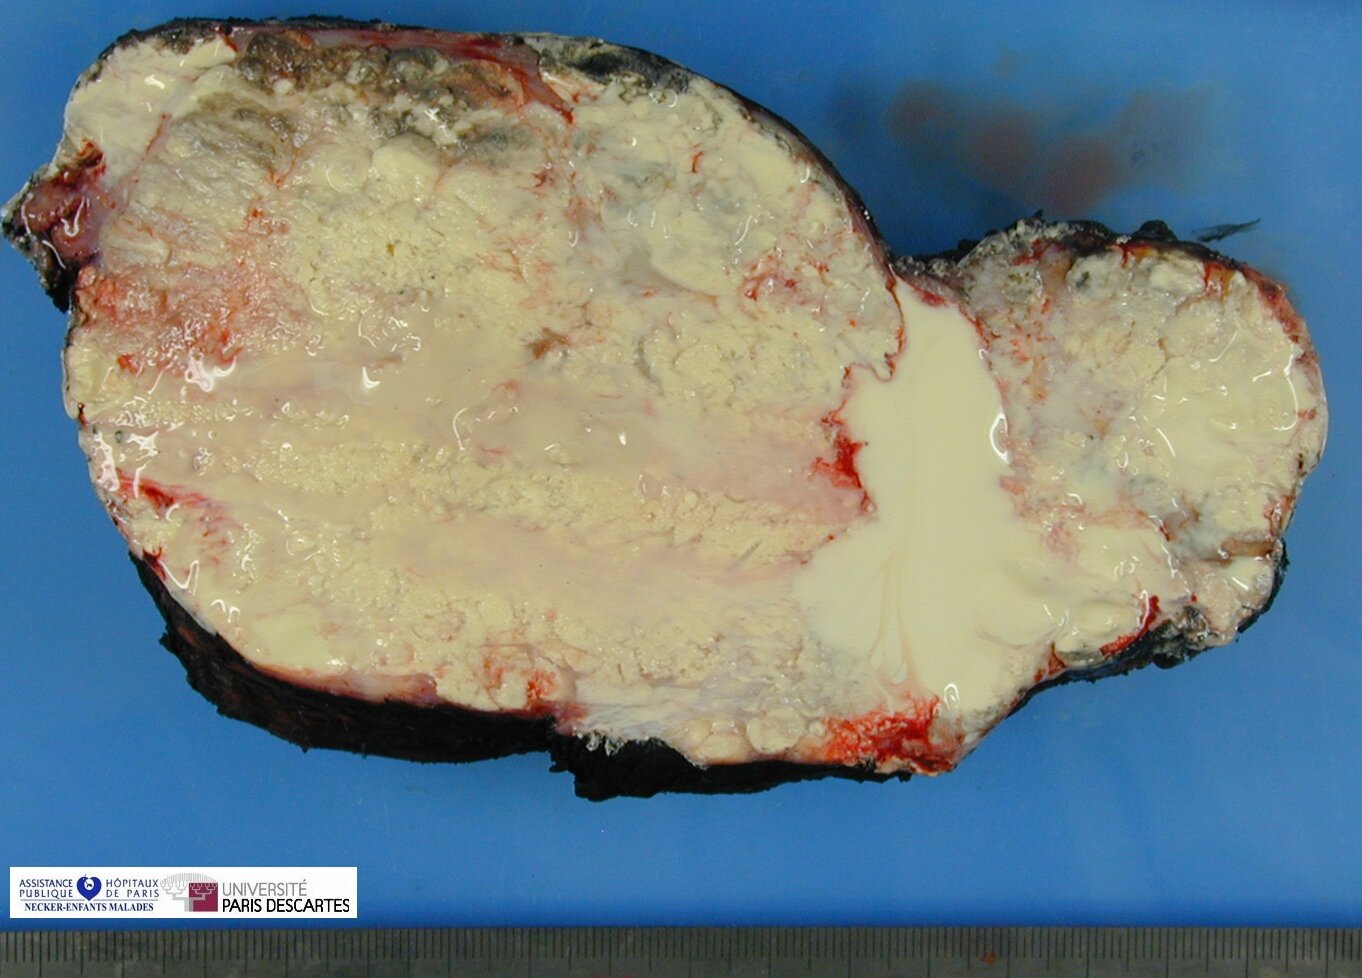

Tumoral Calcinosis